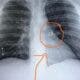

O trabalhador braçal Josian Passos, 37 anos, natural da cidade de Sena Madureira, vem atravessando há meses momentos difíceis. Ele enfrenta uma doença cujo diagnóstico ainda...